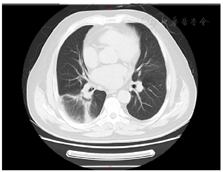

治疗2天后咳嗽喘憋症状未见好转,2019年8月8日行气管镜检查:各级支气管黏膜无充血水肿,少量分泌物。右下叶肺泡灌洗液送检病原学基因检测回报鹦鹉热衣原体。除此之外,影像学上回报:可见右中叶和右下叶晕征和下叶纤维空洞样改变(图1)。根据病原学和影像学结果诊断鹦鹉热衣原体肺炎明确。

文献报道鹦鹉热肺部X线主要表现不同程度的浸润,无特异性,可有眼胸膜下分布的单发结节、实变或磨玻璃影。本例患者存在右下肺单发结节影,但更有特异性反晕征多发磨玻璃影以及右下肺贴近胸膜处的纤维化影,且病原学和血清检测均不支持真菌感染[8,9]。曾有文献报道的鹦鹉热衣原体肺炎的CT表现为右下肺结节伴晕征[10]。更有很多学者认为晕征是Cps的典型表现[11]。关于鹦鹉热的治疗方面,细胞内活性高四环素类为首选药物,或者大环内酯。一般常用四环素500 mg口服,4次/d,7~10天左右症状消失,影像学检测好转。本例患者采用米诺环素100 mg 2次/日,效果明显,症状消失,血常规回报正常。但初期应用碳青霉烯类和喹诺酮类药物治疗效果欠佳。